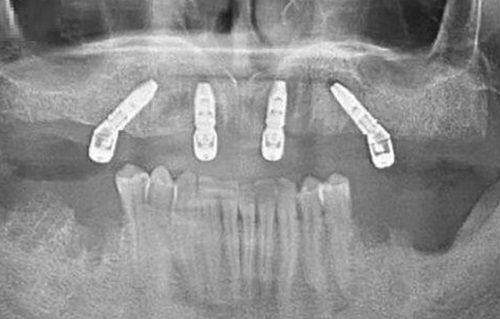

在牙齒矯正方面,正畸同時注重口腔微笑線打造,有隱形正畸、託槽固定正畸、舌側矯正等多種矯正技術,治療方案靈活。種植牙則有“微創種植技術”、“即刻種植技術”及“美學種植技術”三大核心種植技術,種牙速度快,穩定性高,患者痛苦小。兒童顏面管理針對兒童不同年齡段的口腔情況,從咬合、氣道、面型、身型等方面綜合為兒童量身定制個性化顏面管理方案,幫助兒童面型協調發展。

佛山國笑口腔不僅在醫生團隊上實力堅強,在設備方面也十分先進。在種植牙項目上,醫院巨資引進全套數字化影像系統、德國CEREC全瓷美牙系統、口內掃描儀、CAD/CAM義齒研發、雲數據3Dsystems打印、數字化種植系統等優質的口腔醫療設備,可開展前牙、後牙、無牙頜、即刻種植、骨量不足等種植修復技術。牙齒矯正引入了優質的TRIOS數字化印模儀、CBCT、iTero數字化口內掃描儀等設備,能精準採集數據,對於牙齒地包天、牙齒排列不齊等多種問題都有獨特的治療方法。牙周治療也具有優質的治療系統和完善的技術,配有Fotona雙波段雷射、vector微創牙周治療儀、品瑞磁致伸縮牙周治療儀等優質設備,能為牙周患者針對性制定綜合治療方案。